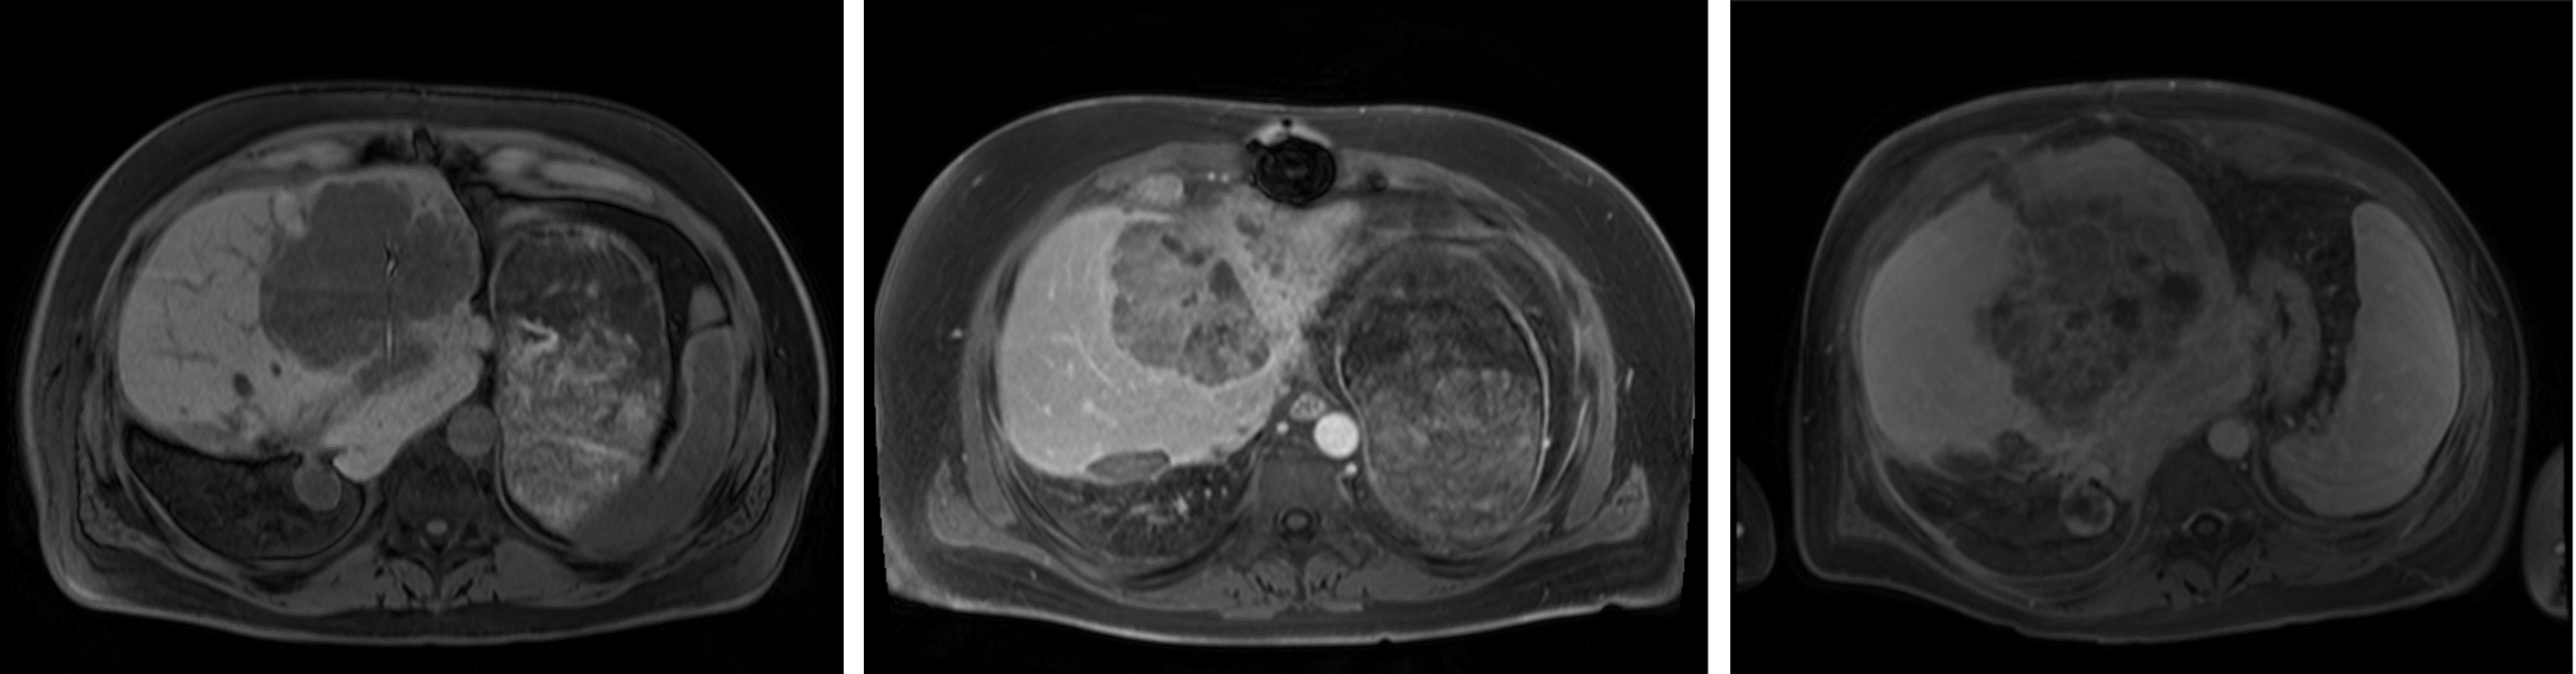

The segmentation performance of the MRI Dropout and MRI Ensemble models improved on that of the MRI UNETR by averaging the predictions (paired t-tests for HD, p=.013𝑝.013p=.013 Dropout, p=.020𝑝.020p=.020 Ensemble; Table 3). Thresholds for OOD detection were set at 95% DSC for all models except the MRI+ UNETR. This model only produced one DSC over 95%, so the threshold was lowered to 80%. 13 images determined to be OOD were shared across the MRI UNETR, MRI Dropout, and MRI Ensemble models. MRI+ UNETR and MRI+ nnU-net performed similarly on MRI+TeTe{}_{\text{Te}}, with MRI+ UNETR achieving a lower HD and MRI+ nnU-net achieving a higher NSD (paired t-tests, p<.001𝑝.001p<.001 all tests). Figure 2 displays visual examples of the segmentation quality of the MRI UNETR.

Refer to caption

Figure 2: Segmentations with high (top) and low (bottom) DSCs along with their corresponding MDs, calculated in conjunction with PCA with two components. Pink is the ground truth segmentation; teal is the MRI UNETR segmentation.

4.2.3 Dimensionality Reduction

Paired with MD, all dimensionality reduction techniques resulted in improvements in the AUROC (t-tests, p=.003𝑝.003p=.003 UMAP/MRI+ UNETR, p<.001𝑝.001p<.001 all other tests; Table 4). On the MRI models, PCA achieved the best performance, outperforming average pooling by 0.14 (±plus-or-minus\pm0.06)% AUROC and 535.11 (±plus-or-minus\pm903.70) seconds. For CT nnU-net, UMAP achieved the best AUROC, outperforming average pooling by 0.09. Figure 2 displays MDs computed on PCA-reduced features, along with the corresponding segmentations. In this figure, higher MDs were associated with poor segmentation performance.